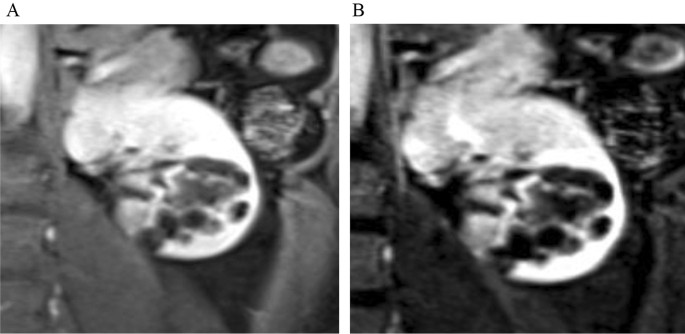

A Mest Up Classification Review Of The Re Classification Of Mixed Epithelial And Stromal Tumor And Adult Cystic Nephroma For The Abdominal Radiologist Springerlink